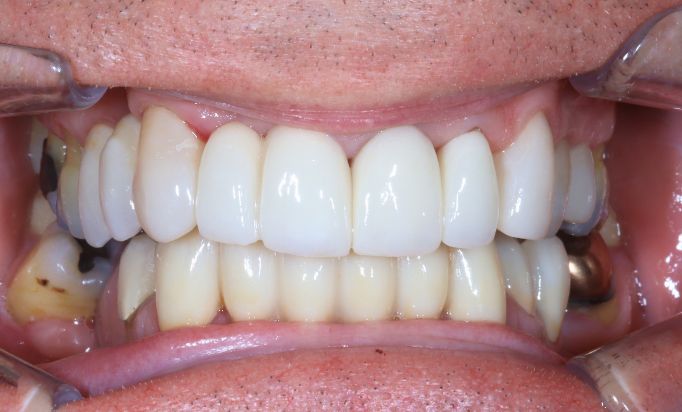

Dental Implants

Rebuild your smile, naturally

Achieve a seamless, natural-looking smile with dental implants.